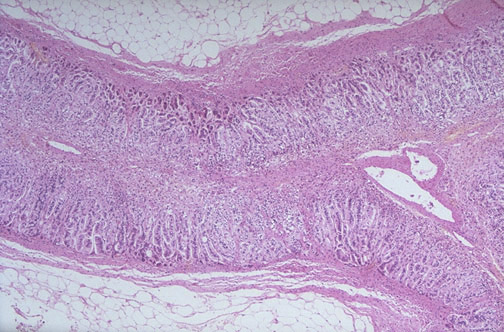

| The most common cause for Addison disease (which is rare) in developed nations is an idiopathic (probably autoimmune) disease leading to atrophy, as seen here. Note that here at low power most of the adrenal is visible. The medulla is not affected. Other autoimmune conditions may also be present, including Graves disease, Hashimoto thyroiditis, and diabetes mellitus. Patients may have weakness, nausea, vomiting, hypotension, skin pigmentation, and weight loss. Laboratory findings include hyponatremia, hypoglycemia, and hyperkalemia. |